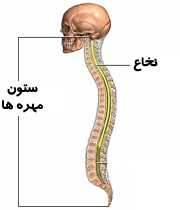

💀ستون مهره : به مجموع 26 استخوان بسیار سخت و مقاوم که در پشت مهره داران قرار دارد و از نخاع نگهداری می کنند ستون مهره می گویند.

💀نخاع : رشته ی بلند و مهم عصبی که در ستون مهره ها قرار دارد و پیام ها را از قسمت تنه و پایین بدن گرفته به مغز انتقال می دهد.

💀جمجمه : به استخوان های سخت و محکم و پهن سر و صورت که از مغز مراقبت می کند جمجمه می گویند.